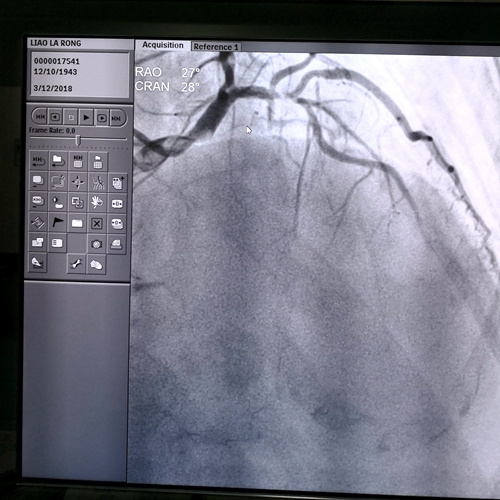

术前造影

廖奶奶目前已行冠脉造影示:右冠慢性完全性闭塞,左前降支近段次全闭,并在病变处植入支架,开通血管,症状也就基本消失了。